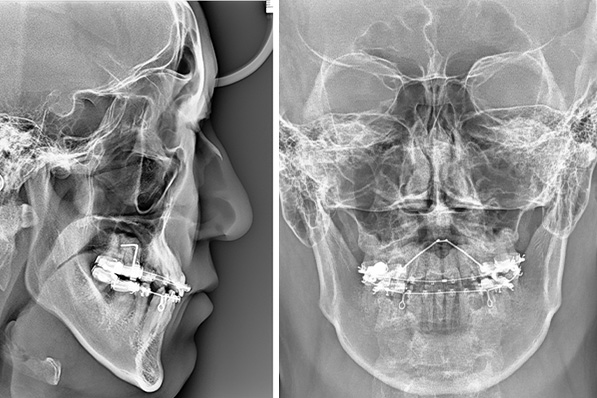

セファロによる骨格分析

セファロは頭部のX線写真を用いて、顎や骨格のバランスを分析する検査です。成長バランスやかみ合わせの状態を多角的に評価でき、歯並びだけでなく将来的な安定性やお顔全体の調和も見据えた治療計画につなげやすくなります。